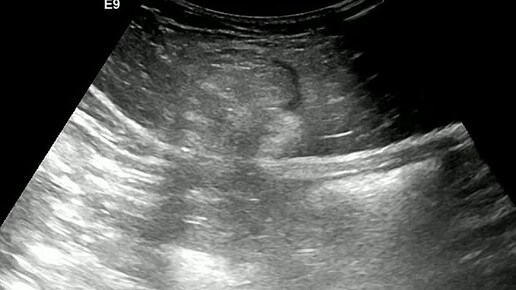

Видео к статье "Ущемленная грыжа белой линии" https://dzen.ru/a/Z4dbuDYQdUQl35Wp

Ультразвуковые находки от врача УЗД Зорина Я.П.